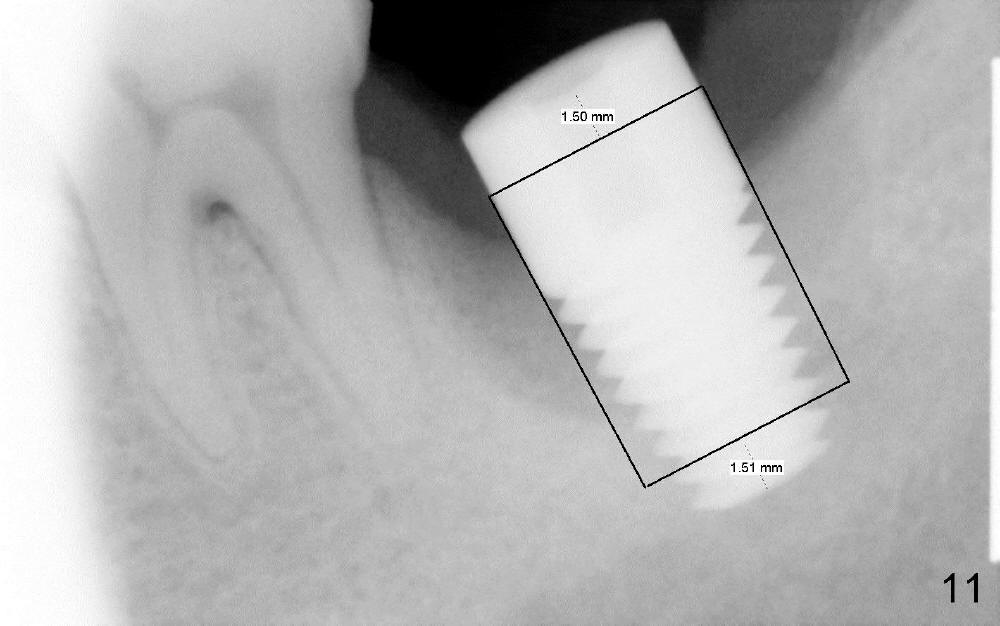

The lower left 2nd molar of a 45-year-old lady has perio-endo disease (Fig.1). The patient is not only very nervous, but also active in gag reflex. It is difficult to take good preop PA (Fig.1 *: ). Root canal therapy is performed. A relatively good PA is taken 1 year postop, again due to gap reflex (Fig.2). The tooth is still nonsalvageable (Fig.3). The last PA is taken 3.5 years before extraction and immediate implant. Infiltration anesthesia is administrated first. The patient experiences pain during early stage of osteotomy, but she does not report readily. Block anesthesia is added. Intraop PAs are taken with difficulty (Fig.4,5 with #1 sensor; 5 mm tap in place). Invasion of the inferior alveolar canal is not noted (Fig.5 dashed line). Oozing is a little more than expected. This is ignored. A 7x14 mm tapered implant is placed; the upper border of the inferior alveolar canal is not intact (Fig.6). Paresthesia area is defined next day (Fig.7). The implant is reversed for a few turns. Paresthesia area is reduced 19 days later (Fig.8). The implant is not stable. Follow up PAs are taken with difficulty (Fig.9-11). It appears that a shorter cylindrical implant is more appropriate for this case (Fig.11). The implant is stabilized with splinting with questionable result (Fig.12).